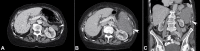

Retroperitoneal liposarcomas are rare tumors arising from the soft tissue of the retroperitoneum and are of mesenchymal cell origin. They can reach a large size prior to causing symptoms and generally have a poor prognosis. We present the case of a 93-year-old lady presenting with a large retroperitoneal liposarcoma at the site of a previous colonic anastomosis for the adenocarcinoma treatment. It caused minimal symptoms initially, but surgical resection was undertaken when the tumor was found to be growing significantly in size. However, due to the tumor's location and its invasion into surrounding structures, the resection was not feasible and subsequently abandoned. A retroperitoneal liposarcoma arising from the site of a previous colonic resection has not been previously described. A review of the diagnosis and current management of these lesions is also given.